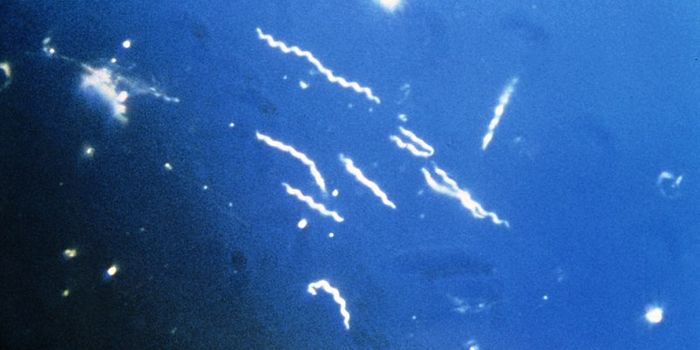

FEB 01, 2021MicrobiologySpirochetes are a type of free-living, spiral-shaped bacteria, some of which are harmless and others that can cause dise ...